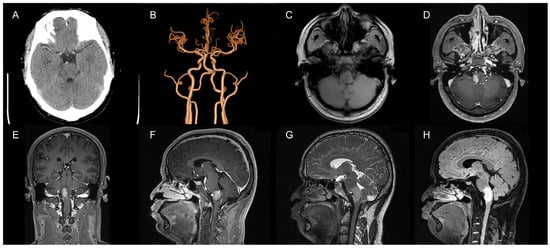

We ruled out the possibility of an intracranial hemorrhagic lesion, which is often associated with increased intracranial pressure, severe headache, or loss of consciousness [6,7,8]. To further clarify the diagnosis, we performed a digital subtraction angiography (DSA) examination, which showed that our preoperative diagnosis was inaccurate and the mass lesion was not caused by a tumor. DSA examinations revealed CCJAVFs, where the right ascending pharyngeal artery acted as the donor artery, and the spinal veins and the occipital cortical veins acted as the drainage veins (Figure 2A–C). The treatment modality should be decided by the anatomical structure and the position of AVF, for which the operation or the intravascular intervention was suitable. The DSA examination suggested that a craniotomy would be unnecessary and that this patient only required management of the arteriovenous fistula. Based on these preoperative findings, an endovascular intervention was performed. A 6F guide sheath was placed through a puncture in the right femoral artery, and a 6F guiding catheter was applied for imaging. The 6F guide catheter was placed at the beginning of the right external carotid artery with the assistance of a guidewire under the roadmap. The contrast media determined that there was no spasm of the vessel. A microcatheter was placed into the site close to the fistula under the road map for embolization, and a spring coil was placed in the superior trunk of the right ascending pharyngeal artery to reduce blood flow and further thrombotic occlusion (Figure 3A,B). The angiogram showed a significant decrease in the blood flow in the superior trunk of the ascending pharyngeal artery. Then, an Onyx biologic gel was injected slowly and intermittently into the upper and lower trunks of the ascending pharyngeal artery through the microcatheter (Figure 3C,D). The diffusion and regurgitation of the Onyx biologic gel were repeatedly observed via microcatheter imaging until the branch at the fistula was completely embolized. The angiogram showed a complete non-visualization of the supply artery and drainage vein, and all intracranial branches were present. Five days after surgery, the DSA analysis showed a complete embolization of the fistula (Figure 4A). The CT examinations showed a lamellar, slightly hypointense shadow in the brainstem, without hemorrhage or ischemia (Figure 4B). The MRI examinations showed lamellar, slightly long T1 and slightly long T2 signals in the brainstem, with a maximum cross-section of about 10 mm × 8 mm. The brainstem mass lesion after treatment was reduced when compared to that before treatment (Figure 4C,D). It is important to note that embolization may pose an additional risk. Dimethyl sulfoxide injection is required prior to embolization and may have potential neurotoxicity. Access vascular injury may occur during embolization. If the biogel enters a vessel other than the lesion site, it may cause cerebral infarction. During embolization, hemodynamic changes also require attention. In fact, immediately after the patient’s surgery was completed, we transferred the patient to the ICU for detailed monitoring as well as an assessment of the patient’s status. After 7 days of monitoring, we confirmed that the patient had no complications and then transferred him to the general ward. The patient recovered well after the operation, and his headaches and hoarseness decreased. He was discharged with a Karnofsky score of 90.

Figure 3.

Intraoperative DSA angiographic treatment of CCJAVF. (A) Microcatheterization through the superior trunk of the ascending pharyngeal artery to reach the lesion; microcatheterization was performed to clarify the fistula. (B) Spring coil embolization of the fistula via the microcatheter; (C) The first microcatheter located in the superior trunk of the ascending pharyngeal artery was used to occlude the fistula with a biologic gel; (D) The second microcatheter in the lower trunk of the ascending pharyngeal artery was used to occlude the fistula with a biologic gel.